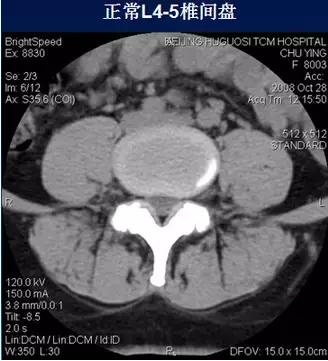

常规腰椎CT扫描L3-S1段,分为

(2)椎间盘层面(软组织窗):观察椎间盘、硬膜囊、神经根、韧带等软组织。